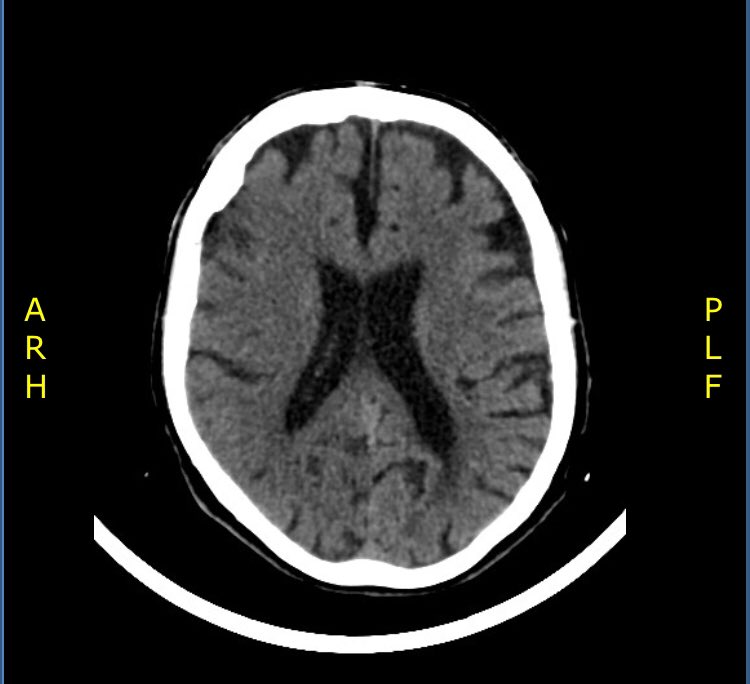

Signos Tomograficos Tempranos Del Infarto Cerebral

Signos Tomograficos Precoces De Isquemia Cerebral En Territorio De Arteria Cerebral Media Pagina 3 De 4 Revista Electronica De Portales Medicos Com